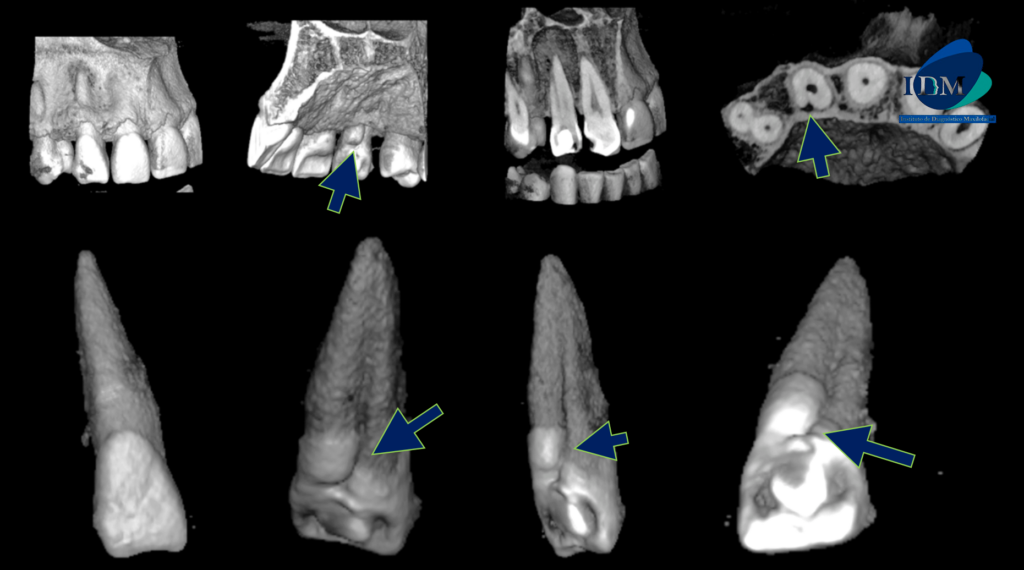

A la evaluación de la tomografía computarizada de campo reducido de la pieza 22 se observa (además de la restauración y la preparación endodontica parcial del conducto pulpar), una alteración de la morfología radicular caracterizada por la presencia de un surco palatino que va desde tercio cervical hasta el tercio apical y que ocasiona el ensanchamiento del espacio para el ligamento periodontal (vista en corte axial y transaxial), asimismo se observa la presencia de un proceso osteolítico periapical que ocasiona el adelgazamiento de las tablas óseas vestibular, palatina y del piso de fosa nasal de aparente origen endoperiodontal.

RECONSTRUCCIÓN 3D

- Sindesmo corono radicular.